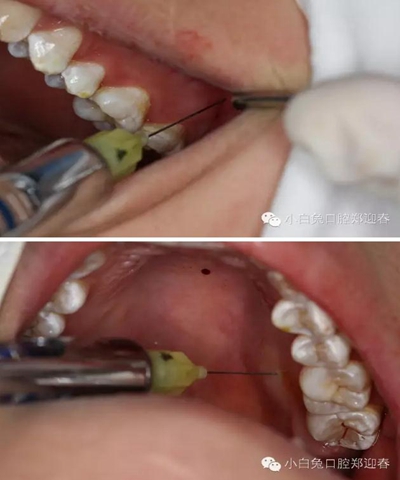

利用微創(chuàng)拔牙標準進行阻力冠切割

切割過程對冷卻和角度的要求,一定要是水柱的噴射。

渦輪動力切割阻力牙冠

“T”型分割近中阻力冠

分別去除近中阻力冠的頰和舌部的牙冠